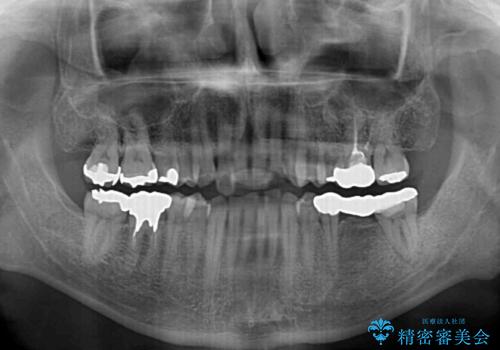

- 近医にてブリッジ治療を行った歯が痛くてたまらないとのことで来院された患者様です。

診察を行ったところ、奥の土台になっている歯は神経組織が失活しており、根尖部に病変があり、そこが原因で痛みを生じている状態でした。

根管治療を行うためにブリッジを除去したところ、むし歯が歯肉の奥深くにあまで及んでいたため、歯周外科処置によりむし歯が歯肉縁より浅い位置へと改善することとしました。